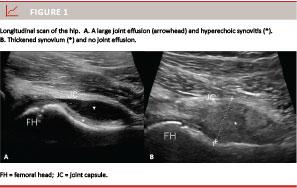

The definitions of US pathology used were those of the OMERACT 7 group [7], which are also applied for children [9]. Joint effusion is defined as abnormal anechoic or hypoechoic (relative to subdermal fat) intraarticular material that is displaceable, compressible and without Doppler activity (Figure 1 A).

Synovial hypertrophy is defined as abnormal hypoechoic (relative to subdermal fat), but sometimes isoechoic or hyperechoic, intraarticular tissue that is nondisplaceable and poorly compressible (Figure 1 B). Doppler activity is a marker for the degree of inflammation.